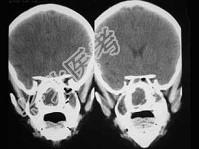

- 单项选择题女,14岁,渐进性鼻塞2年余,右眼肿痛数月,CT如图所示,应诊断为 ( )

A、筛骨骨肉瘤

B、筛骨骨纤维瘤

C、筛骨软骨瘤

D、筛骨结核

E、筛骨骨化性纤维瘤